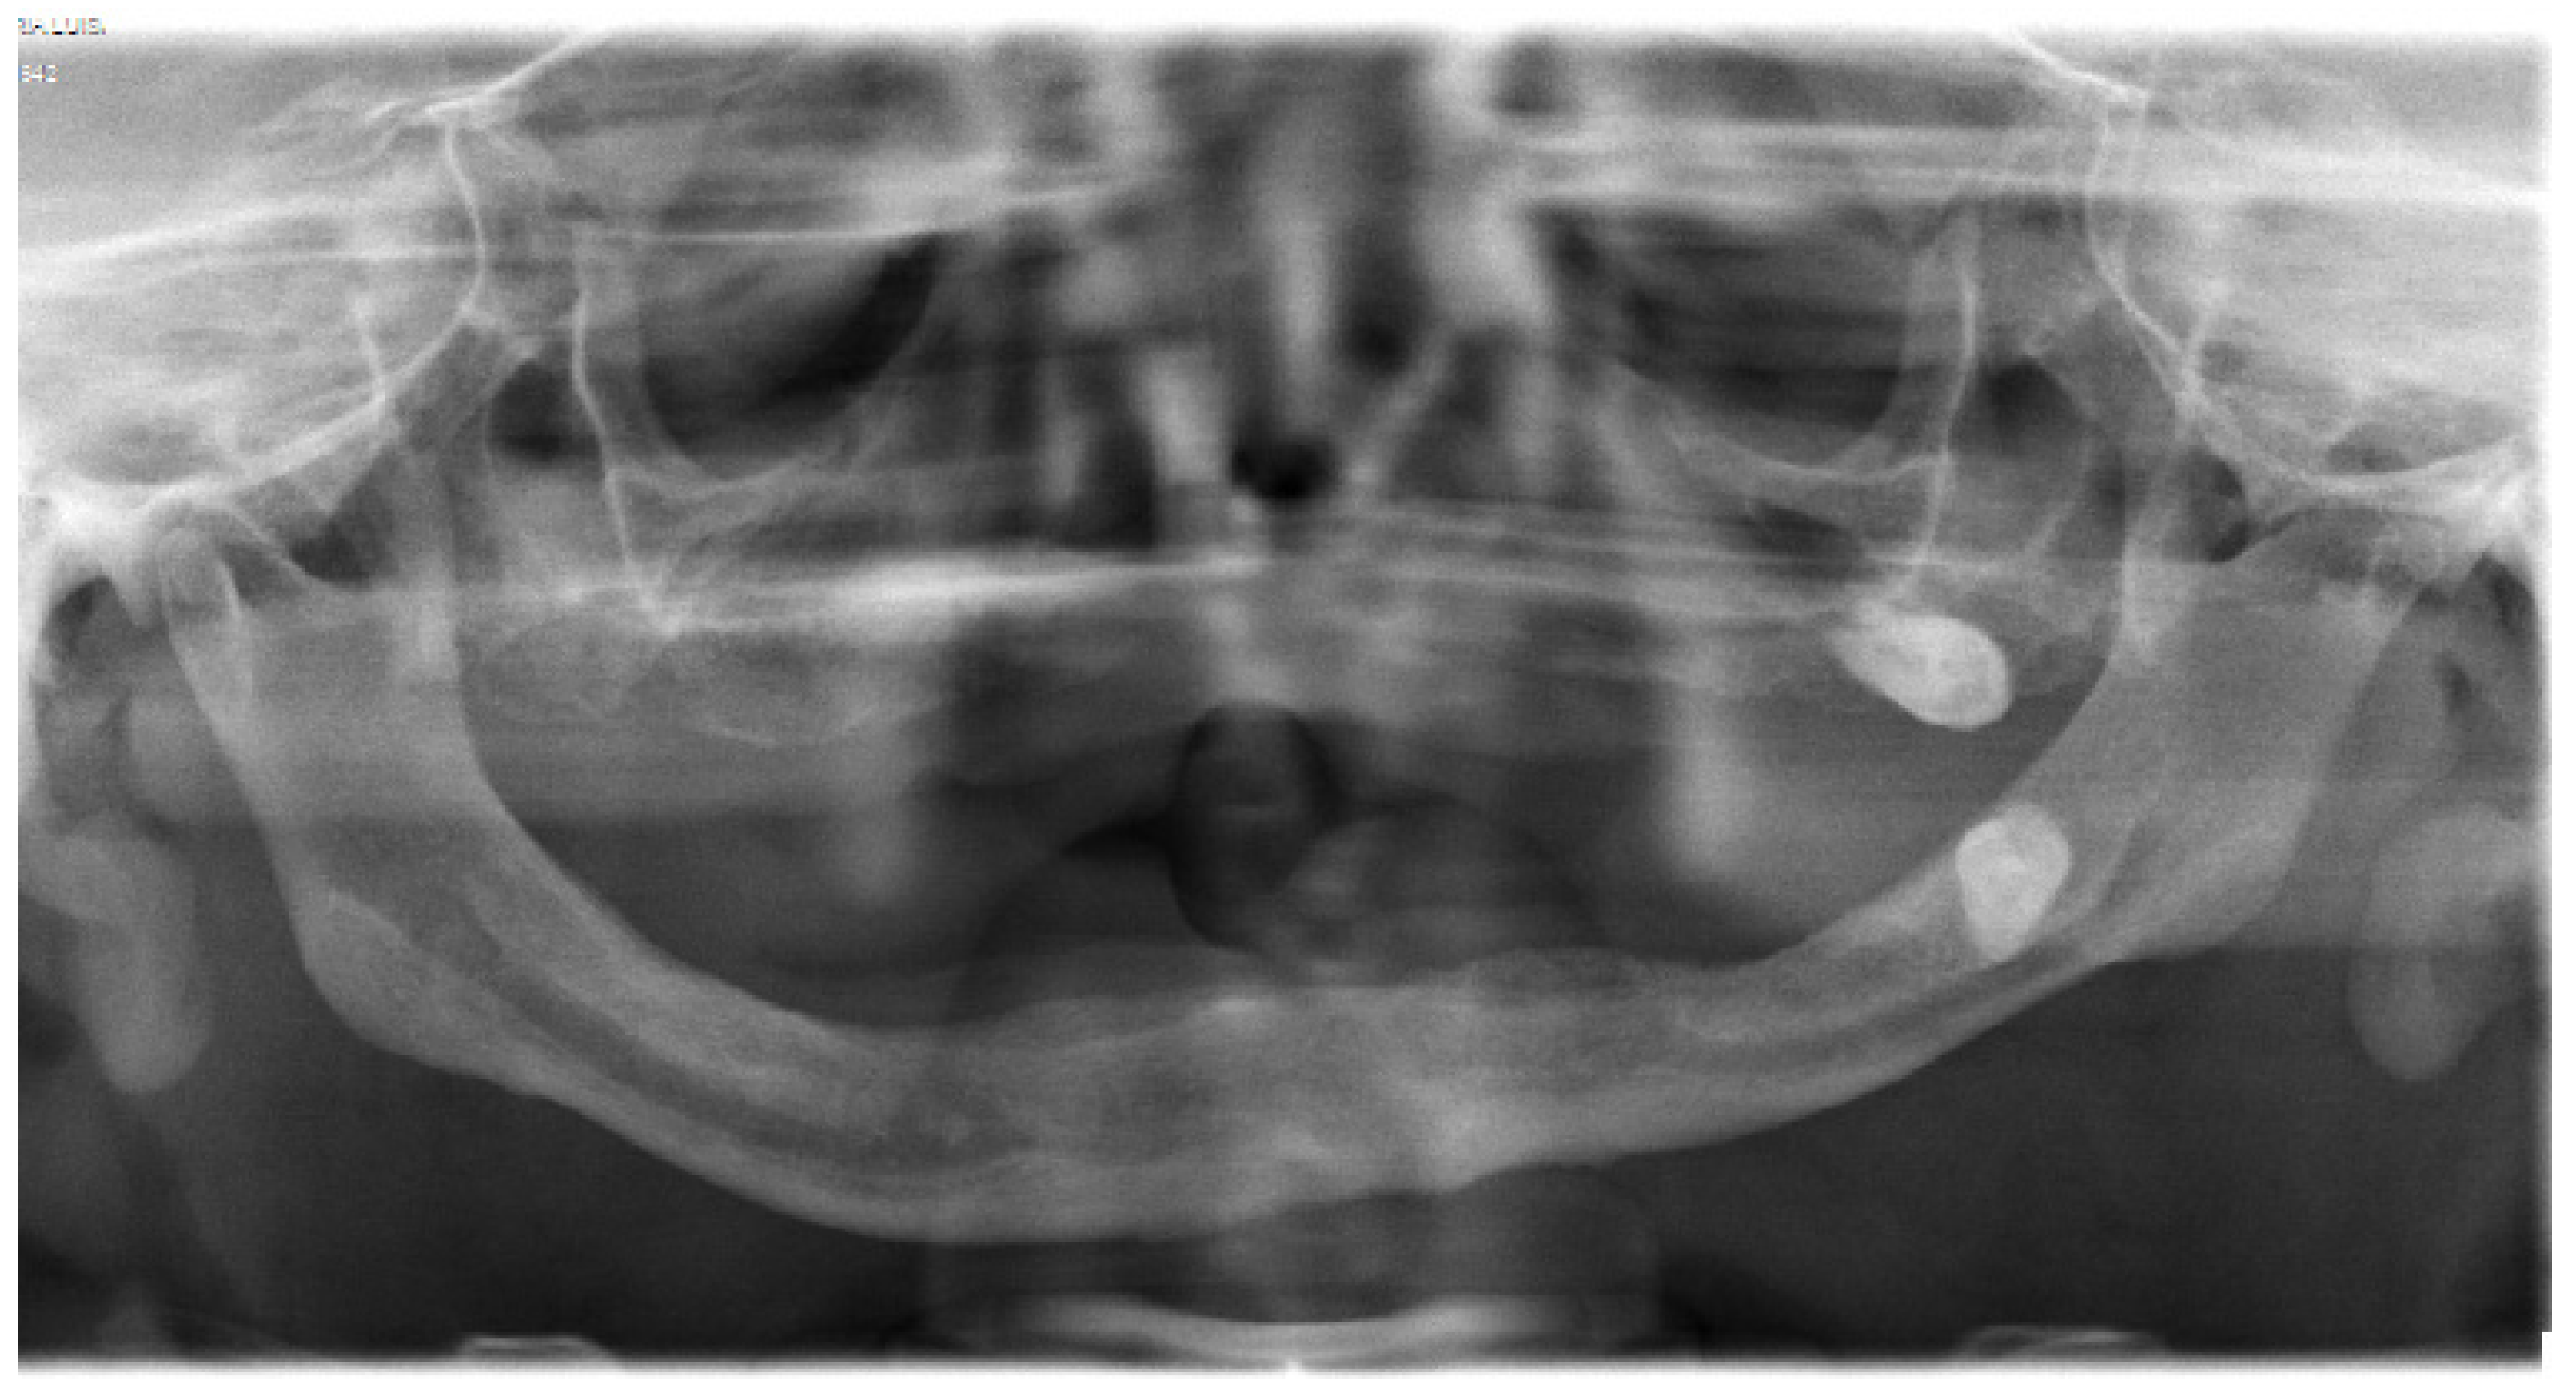

8. Maxilofacial Features

In 2011, the patient herself sought treatment as she had a complete loss of teeth and an extreme maxillary atrophy. She requested surgical intervention for the implant of teeth. However, an orthopantomography confirmed the high degree of atrophy, describing very fine alveolar edges and type IV maxillomandibular atrophy. Due to the state of the jaw bones, the surgical intervention was not considered (Figure 5).

Figure 5.

Orthopantomography of patient.